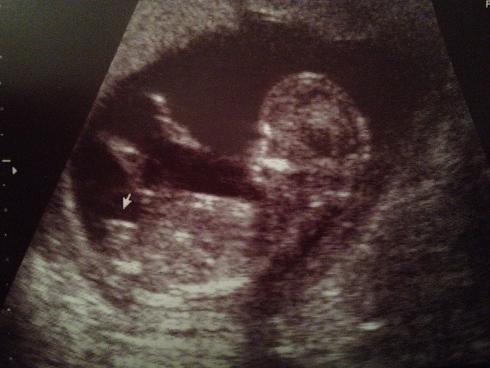

Attachment 11205 Attachment 11206 Attachment 11207

AAA I think girl!!!! Beautiful baby!!!!!!!

Looks like a little girl - congrats crystalclear!

Does look girly :)

Maybe pink.

I think girl x